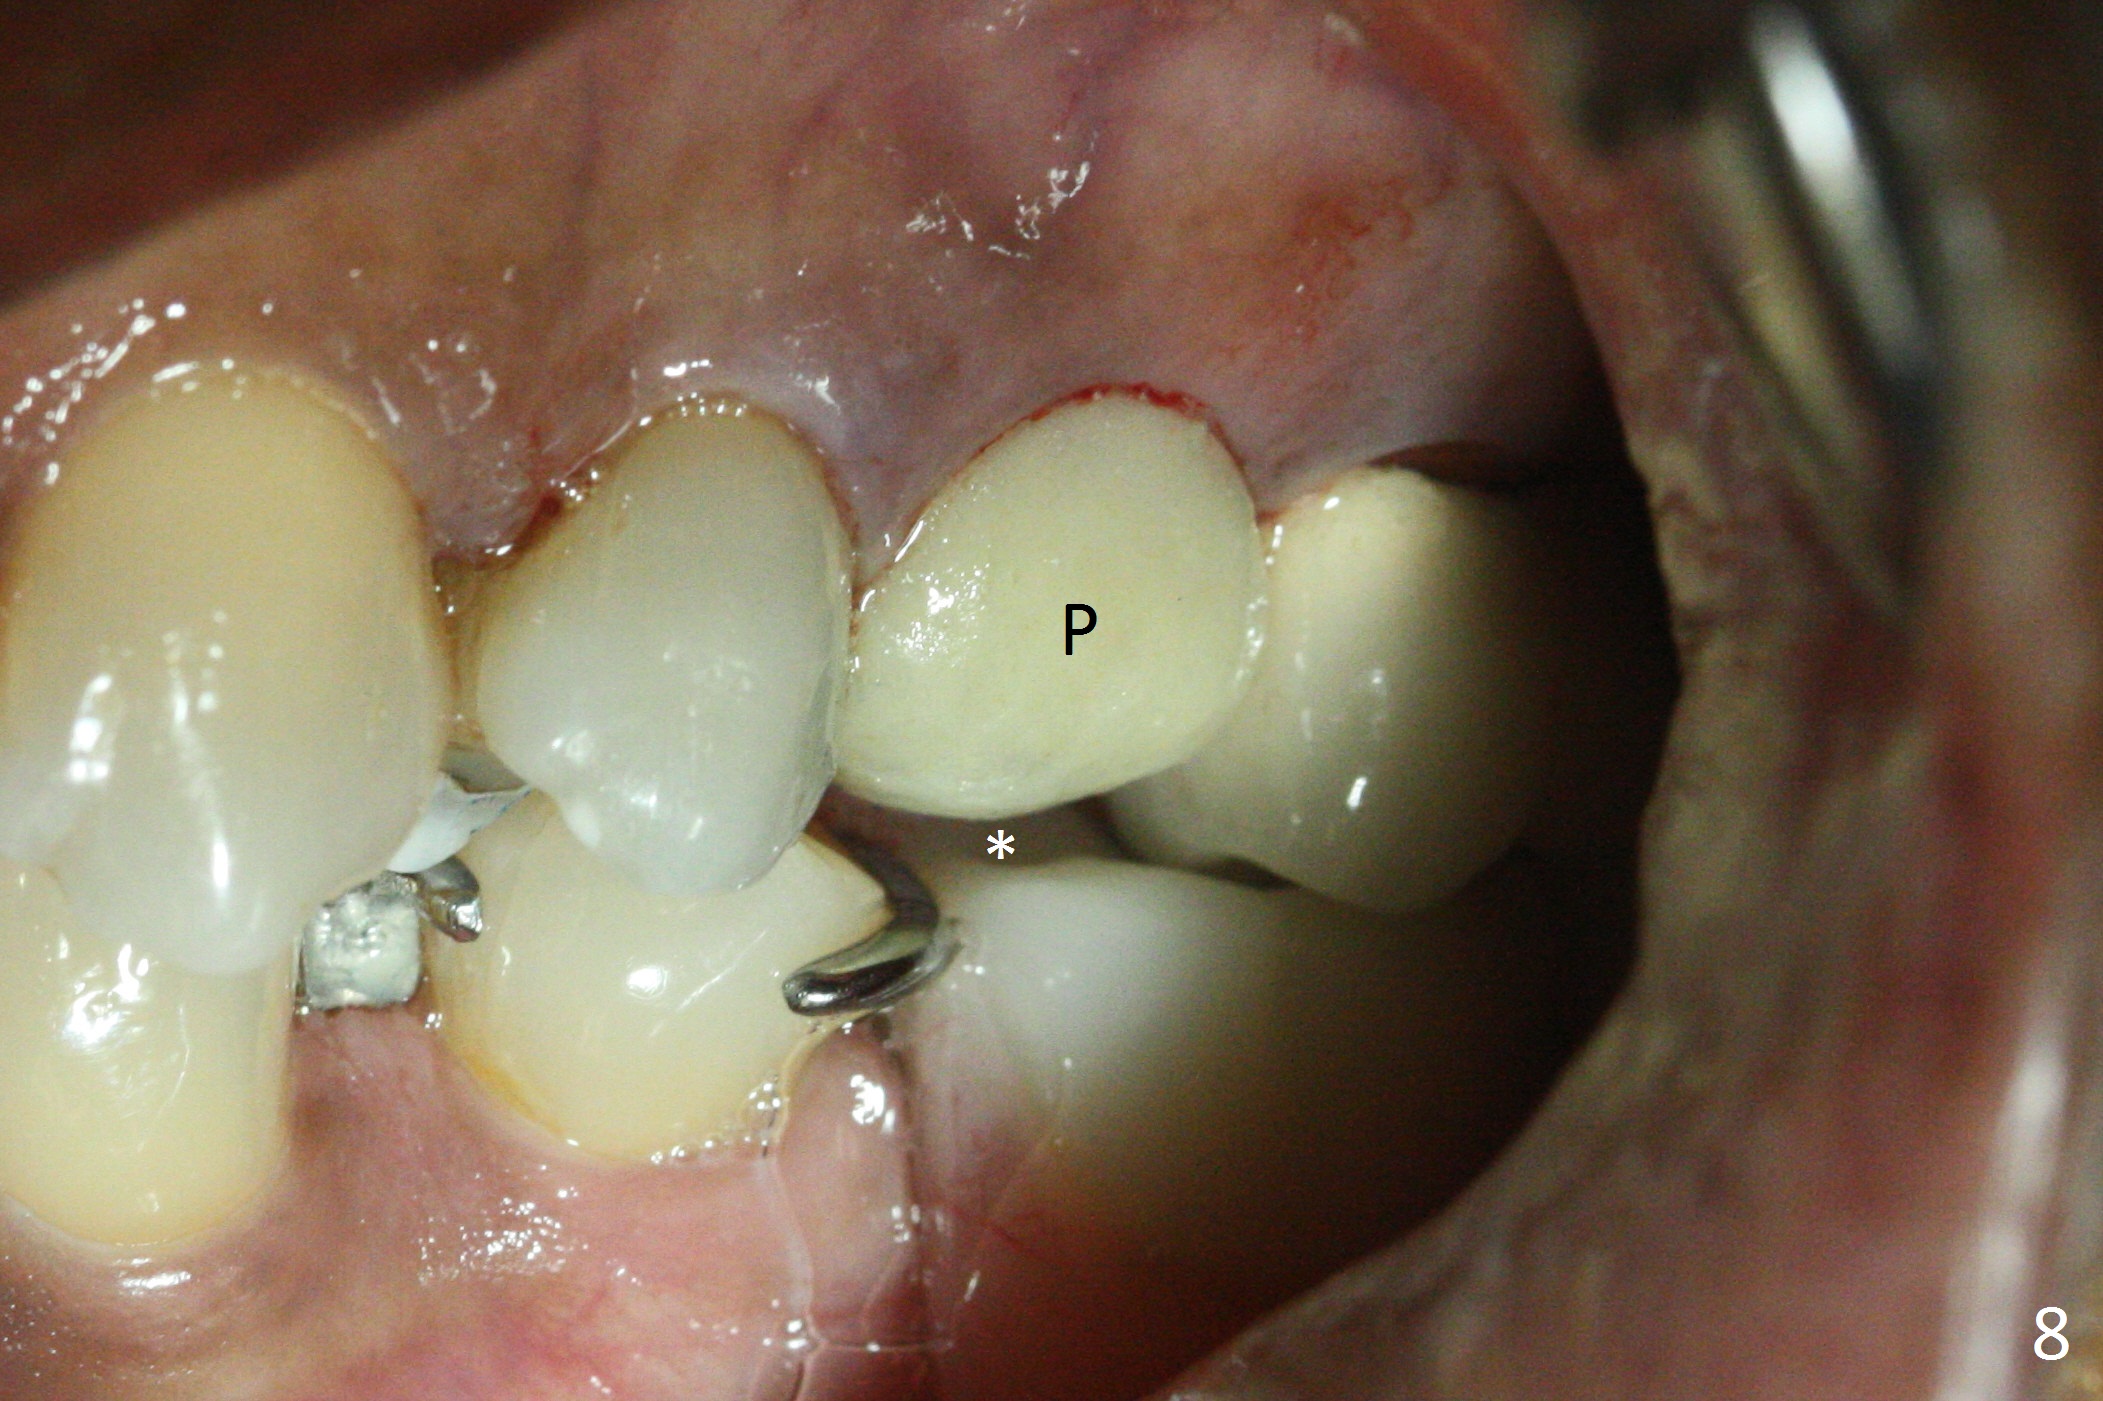

Since the apical native bone is limited at #13 after extraction, no PA is taken until a 4x11 mm dummy implant is placed after 1.6 mm and 3.3 mm drills for 13 mm (Fig.1). After using Lindamann bur to move the osteotomy distal and reusing 3.3 mm drill, the trajectory of a 4.5x11 mm IBS dummy implant improves (Fig.2,3 with low stability). When the implant is removed, the buccal portion of the socket is found to be perforated (Fig.4 P). Although the reason for the perforation is unknown, it is repaired by insertion of a piece of PRF plug, followed by allograft. #1 and 2 in Fig.4 represent the 1st and 2nd osteotomies, as shown in Fig.1 and 2, respectively. The trajectory of the final 5x13 mm implant is acceptable (Fig.5-7, different angulations), so is insertion torque (45 Ncm). After placing a 5.5x4(4) mm abutment, an immediate provisional is fabricated (Fig.8 P) with occlusal clearance (*). The interdental papillae remain in place 12 days postop (Fig.9 *). There is no sign of postop sinus infection. The provisional is loose 18 days postop; the abutment is changed to 5x4(3) mm (Fig.10). It is difficult to catch the mesial margin of the abutment for impression 4 months postop, due to poor oral hygiene and the short cuff (3 mm, Fig.11). The appointment for impression is rescheduled with emphasis on oral hygiene and no wearing the provisional for a few days prior to next appointment. Bone has grown into the space between the 1st and 2nd threads 5 months post cementation (Fig.12) and the bone is normal, solid and dense 2 years 11 months post cementation (Fig.13 >). There is mesial open margin of the tooth #14 (Fig.13,14 *).